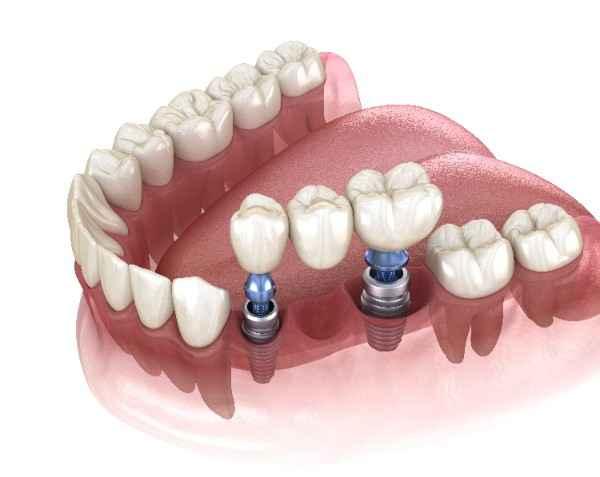

Dental implants are titanium or zirconia posts surgically inserted into the jawbone to replace lost tooth roots. Once integrated with bone — a process known as osseointegration — they provide a stable foundation for crowns, bridges, or dentures. This crucial stability is what makes dental implants Blackburn a natural alternative to traditional removable dentures or bridges.

Unlike conventional dentures that might slip while talking or eating, implants fuse securely into the jawbone. This creates a foundation that functions much like natural tooth roots. As a result, patients often regain the confidence to smile, laugh, and speak without self-consciousness.

Modern implant planning uses 3D imagery and computer-guided placement to ensure optimal positioning. Each implant is customised to suit your bone density and bite pattern. This precision means that your replacement teeth sit in the correct alignment, which directly supports proper speech and chewing performance.